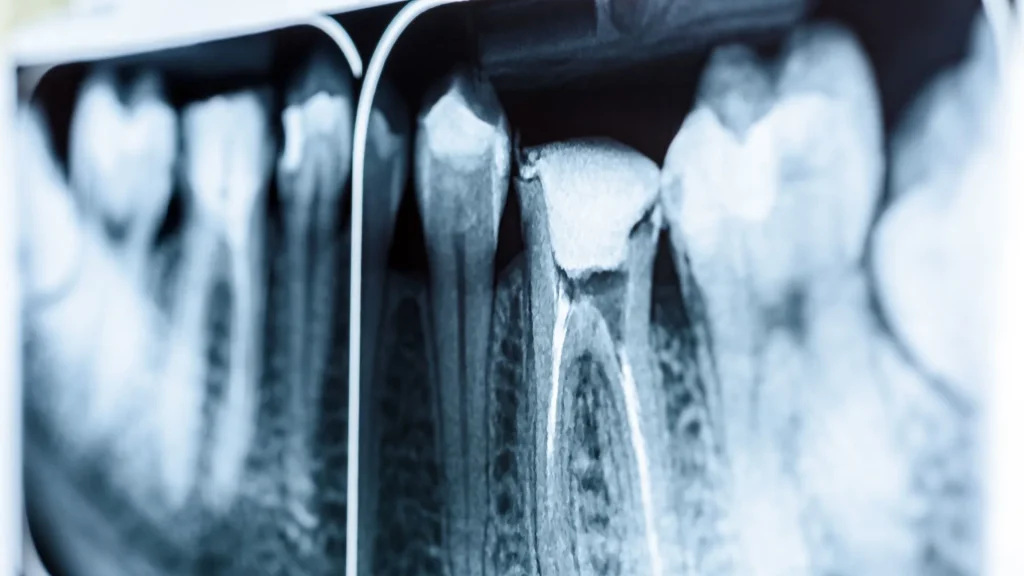

Digital imaging hadir sebagai solusi modern dalam radiologi. Hasil gambar dapat ditampilkan langsung pada layar komputer tanpa perlu proses pencucian film, membuat diagnosis lebih efisien.

Keunggulan X-Ray Digital

Sistem digital menawarkan kualitas gambar yang lebih tajam, dapat diperbesar, dan dianalisis dengan lebih detail. Hal ini membantu dokter dalam mendeteksi penyakit dengan tingkat akurasi lebih tinggi.